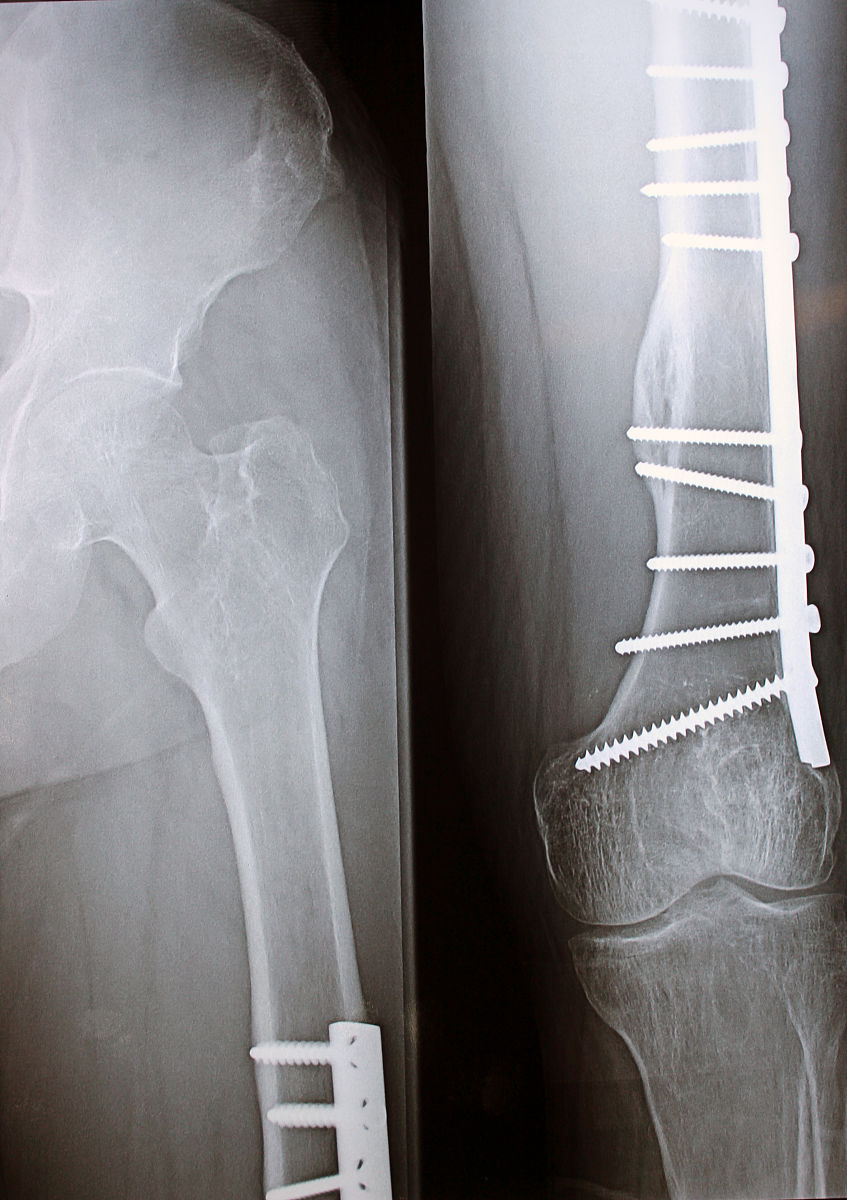

• 优点:AO内固定是通过内部置入的金属装置来稳定骨折骨片,具有较高的稳定性和牢固性,可以促进骨愈合,减少不良骨折愈合的风险。

综上所述,评价AO内固定好还是外固定好需要考虑多个因素,如骨折的类型、位置、患者的年龄、骨质状况等。一般而言,AO内固定在提供更好的稳定性和促进骨折愈合方面具有优势,但外固定对于某些特殊情况可能更适用。医生会根据具体情况和患者需求来决定采用哪种固定方式。